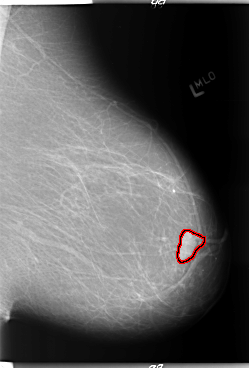

FILE: B_3011_1.LEFT_CC.OVERLAY

TOTAL_ABNORMALITIES 1

ABNORMALITY 1

LESION_TYPE MASS SHAPE LOBULATED MARGINS CIRCUMSCRIBED

ASSESSMENT 4

SUBTLETY 5

PATHOLOGY BENIGN

TOTAL_OUTLINES 1

BOUNDARY